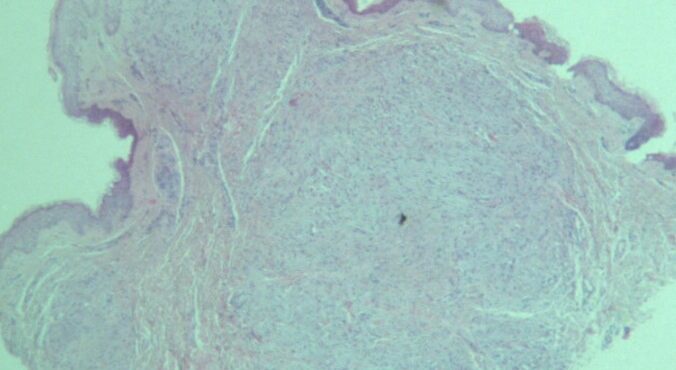

Necrobiois lipoidica diabeticorum = النخر الشحماني السكري Necrobiosis Lipoidica Necrobiosis lipoidica is an idiopathic disorder typified by indurated plaques of the shins . In 1966, in a large series, Muller and Winkelman reported that two thirds of patients with necrobiosis lipoidica had overt diabetes at the time of diagnosis {82}. Of the rest, all but […]